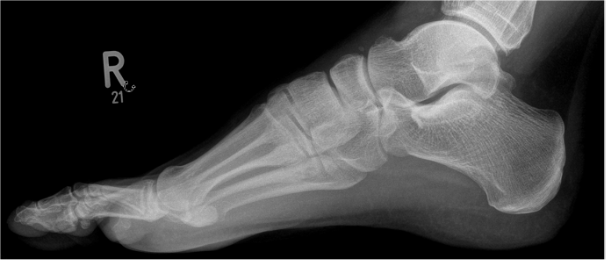

Röntgen Fuß rechts seitlich

Ein 37-jähriger Patient stellt sich mit hinkendem Gangbild in Ihrer Notfallambulanz vor. Er berichtet am Abend zuvor bei Freunden gewesen zu sein und auf dem Rückweg (beim Heruntersteigen der Treppe) die letzte Stufe nicht gesehen zu haben. Es trat ins Leere und erlitt ein Distorsionstrauma des rechten Fußes. Aufgrund der initialen Schmerzen begann der Patient sofort mit der Kühlung des Fußes. Zu dem Zeitpunkt war das Stehen und gehen unter Schmerzen möglich. Gegen Abend und in der Nacht nahmen die Beschwerden zu, der Patient konnte nicht mehr gehen und nahm eine Tablette Ibuprofen 800mg ein.

Nun erfolgt die Vorstellung bei noch persistierenden Beschwerden, jedoch ist das Gehen unter Schmerzen wieder möglich. Relevante Vorerkrankungen oder Allergien bestehen nicht. Eine Dauermedikation wird nicht eingenommen.